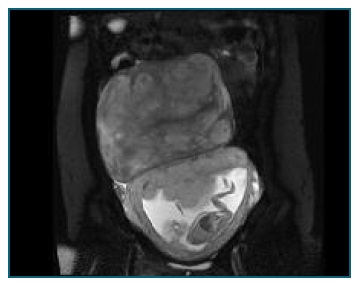

An abdominal ultrasound was performed and revealed a solid mass, measuring 18.1 x 18.0 x 10.0 cm, with sparse vascularization and myometrium-like echogenicity. To better characterize the lesion, magnetic resonance imaging (MRI) of the abdomen and pelvis was requested and showed a 18.5 x 17.8 x 10.9 cm mass, attached to the uterus, with an isointense to the myometrium lesion in T1 weighted images and a heterogenous lesion in T2 (Figure 1). Administration of intravenous gadobutrol contrast suggested a cystic component. The upper limit of the mass was located at D12-L1 level and compressed the inferior right renal pole, not causing hydronephrosis nor anatomical distortions.

Figure 1 Magnetic resonance image: T2-weighted image showing a heterogeneous lesion measuring 18,5 cm in diameter, occupying the upper abdomen of a 16 weeks pregnant woman.